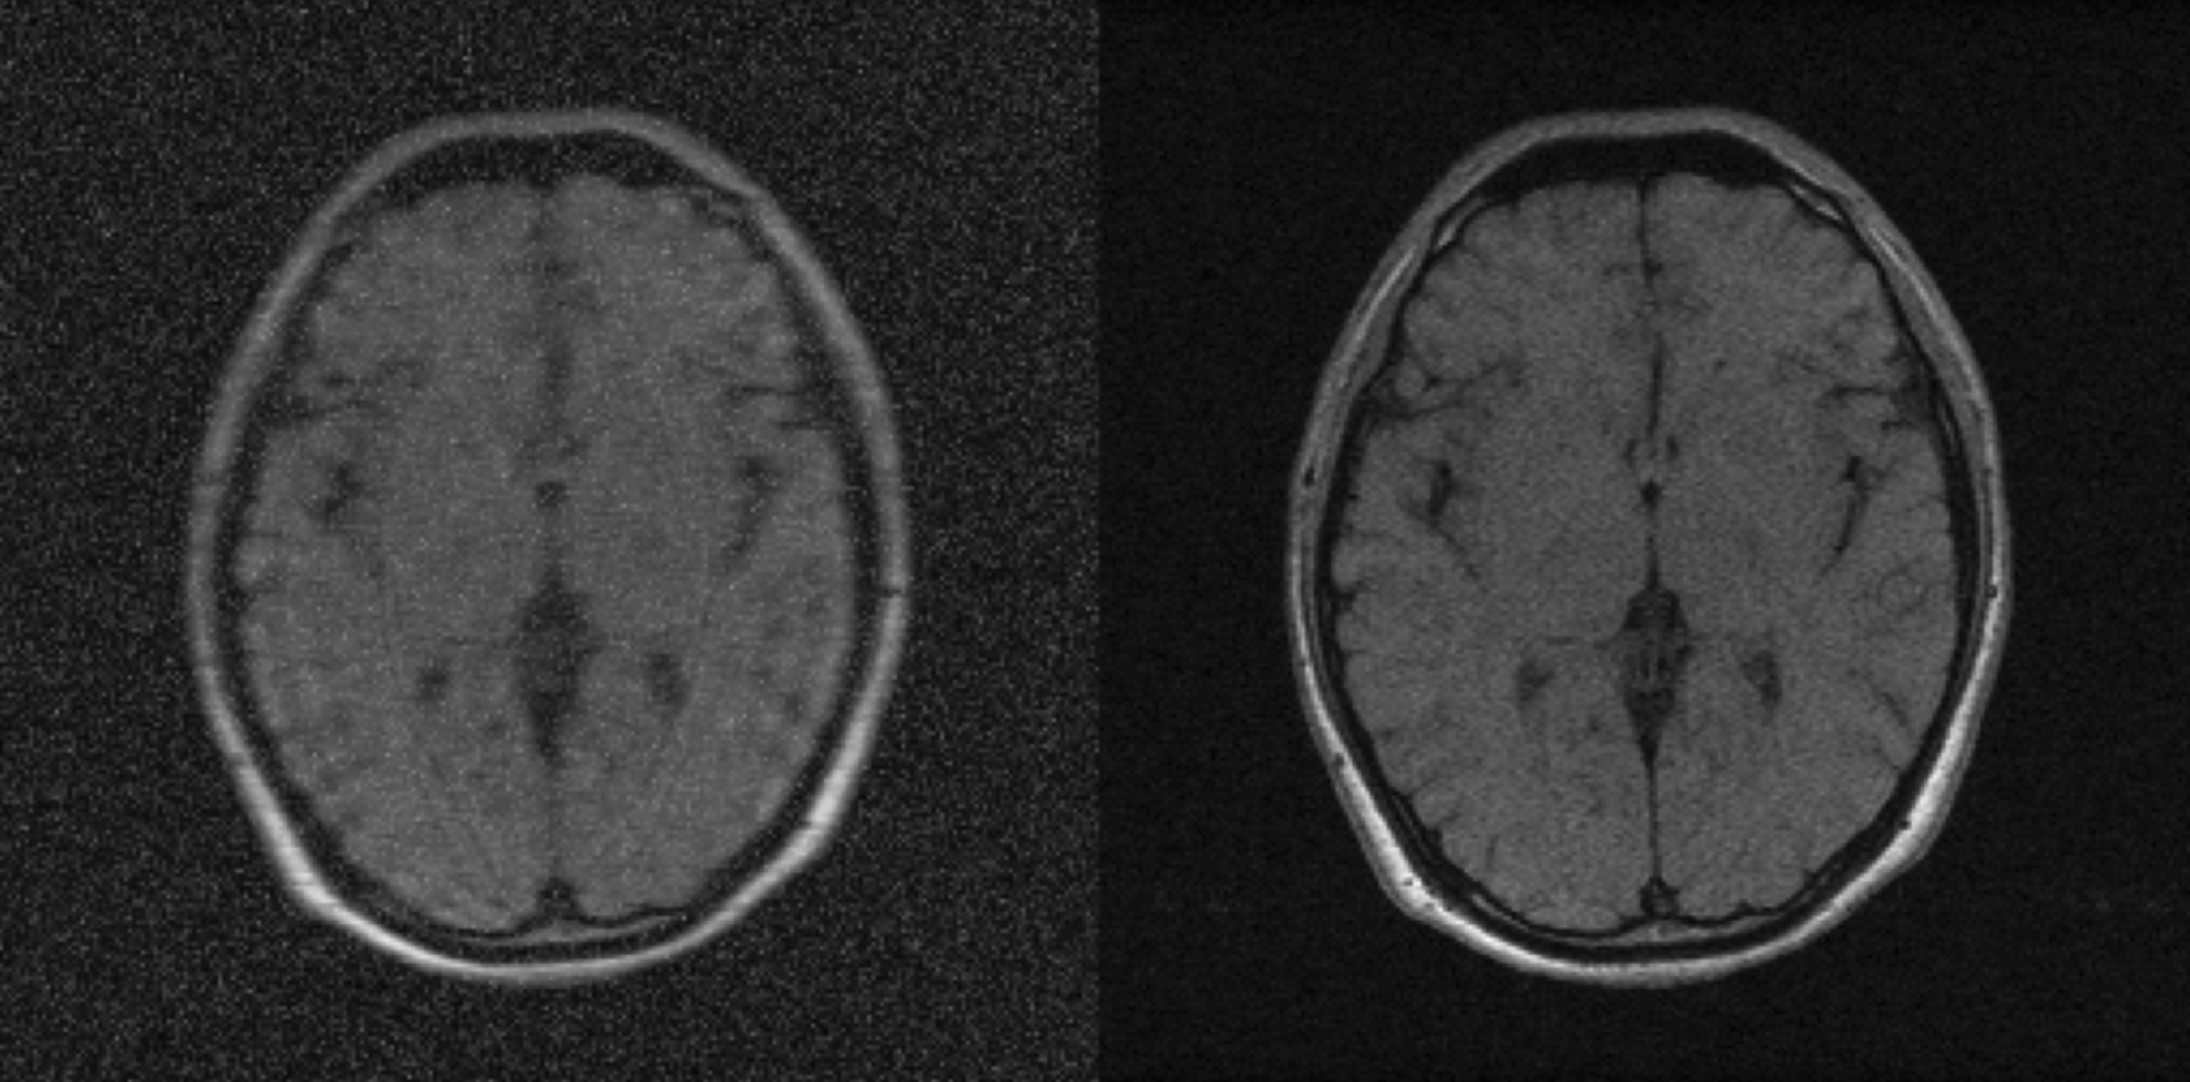

Left: the simulated image(after downsampling and adding rician noise) as input; Right: the acquired HR images